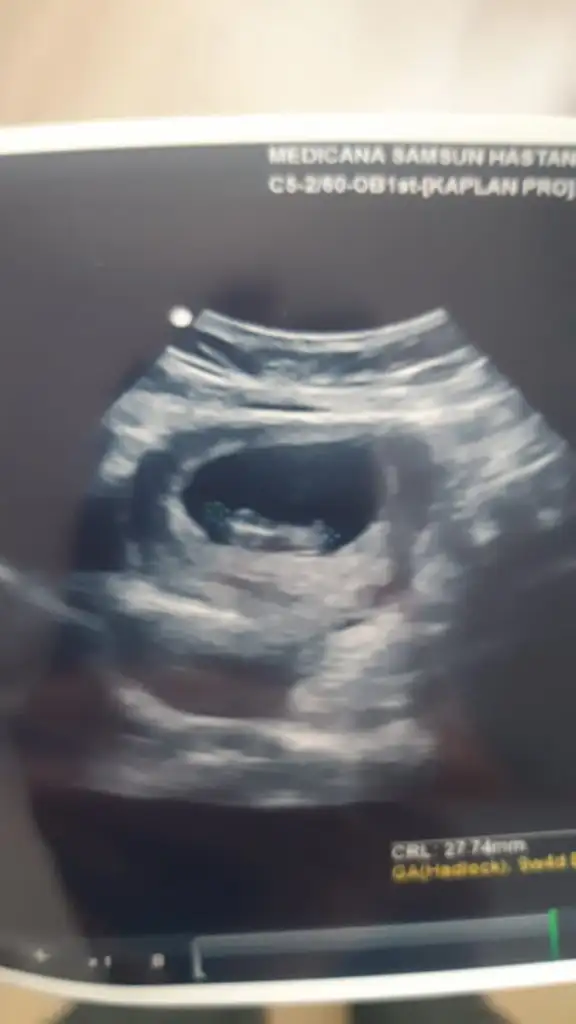

Tam 9. Haftada karından ultrason görüntüsü. Cinsiyeti ne olabilir, ben de merak ettim😊 Pasha22 Pasha22